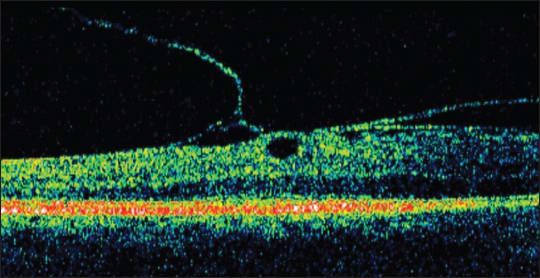

Nineteen eyes of 18 patients were retrospectively diagnosed with LMH based on UHR OCT criteria similar to those described above, namely (1) an irregular foveal contour, (2) a break in the inner fovea, (3) separation of the inner from the outer foveal retinal layers, leading to an intraretinal split, and (4) absence of a full-thickness foveal defect with intact photoreceptors posterior to the area of foveal dehiscence (Figure 1).

Figure 1. SD-OCT demonstrating lamellar hole features described by Witkin et al.8 The OCT demonstrates an irregular foveal contour, a break in the inner fovea, an intraretinal split with bridging columns and the absence of a full thickness foveal defect. An ERM is also present.

Stratus OCT, which was also performed on the study eyes, was also able to demonstrate the four OCT criteria for LMH diagnosis in all 19 eyes. However, UHR OCT revealed additional structural details not visible on the Stratus OCT. For example, UHR OCT demonstrated that the intraretinal split occurred either between the high backscattering OPL and the low backscattering ONL or within the OPL in all 19 eyes. Additional findings seen on UHR OCT included ERMs, vitreomacular traction, and a visibly detached posterior hyaloid above the macula.